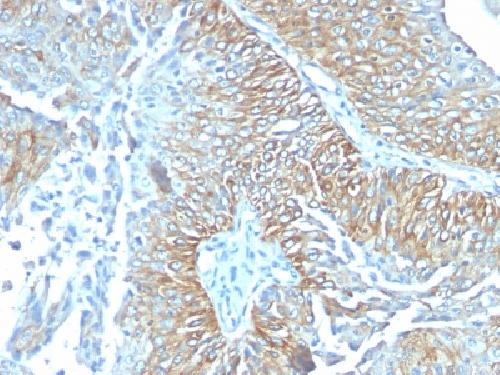

TRIM29 (Lung Squamous Cell Carcinoma Marker) Antibody

| Description | TRIM29 (Lung Squamous Cell Carcinoma Marker); Clone TRIM29/1041 (Concentrate) |

| Application notes | A431 cells. Tonsil or Squamous cell carcinoma. |